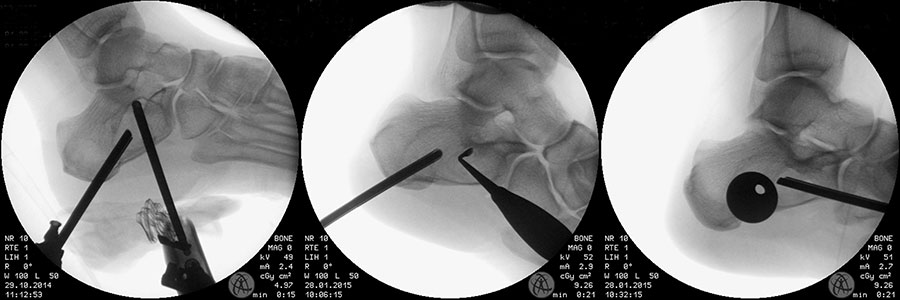

Axiale CT-Aufnahmen eines Osteoidosteoms im Bereich des Calcaneus mit typischer Nidusbildung und perifokaler Sklerose (links). Bildgesteuerte Thermofrequenzablation der Läsion (rechts).

Abbildung 6

Die Computertomographie (CT) wird seltener als die MRT herangezogen um eine spezi­fischen Artdiagnose zu finden, liefert aber wertvolle Informationen zur Kortikalis­beschaffen­heit (Kontinuität, Stärke, enostale Arrosion) unterschiedlichster Knochenläsionen. Insbe­sondere die enostale Kortikalisarrosion, wie sie häufig bei chondrogenen Tumoren anzu­treffen ist, kann konkrete Hinweise liefern, die in Zusammenschau mit histologischen Befunden zu einer definitiven Diagnose führen (siehe Spezifische Entitäten: Enchondrom vs. atypischer chondrogener Tumor/Chondrosarkom). Die Computertomographie ist außerdem hilfreich in der Abgrenzung komplexer anatomischer Strukturen (z.B. 3D-Rekonstruktion) und sehr kleiner Knochenläsionen. Bei der Diagnose des Osteoidosteoms bleibt die CT Mittel der Wahl um die charakteristischen Veränderungen in der bildgebenden Diagnostik exakt darzustellen (Abb. 6). Die Gewebedichte von weichteiligen Tumoren, insbesondere von intra- und extraossären Lipomen, kann im Vergleich zum subkutanen Fettgewebe mithilfe der Houndsfield-Skala beurteilt werden.